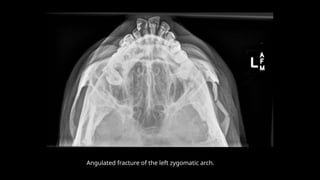

Angulated fracture of the left zygomatic arch.

z Submentovertical view  Itis an angled inferosuperior radiograph of the base of skull.  Any cervical spine pathology should be ruled out before performing this view.  If erect, patient sits and leans back head facing away from the receptor.  If supine use pillow to elevate and tilt head backwards.  The head is tilted until IOML is parallel to the receptor and the vertex is in contact with the receptor. Beam centred 4cm inferior to mental point. • collimation • anterior to include mandibular mentum • posterior to include occipital bone • lateral to include the skin margin

Angulated fracture ofthe left zygomatic arch.